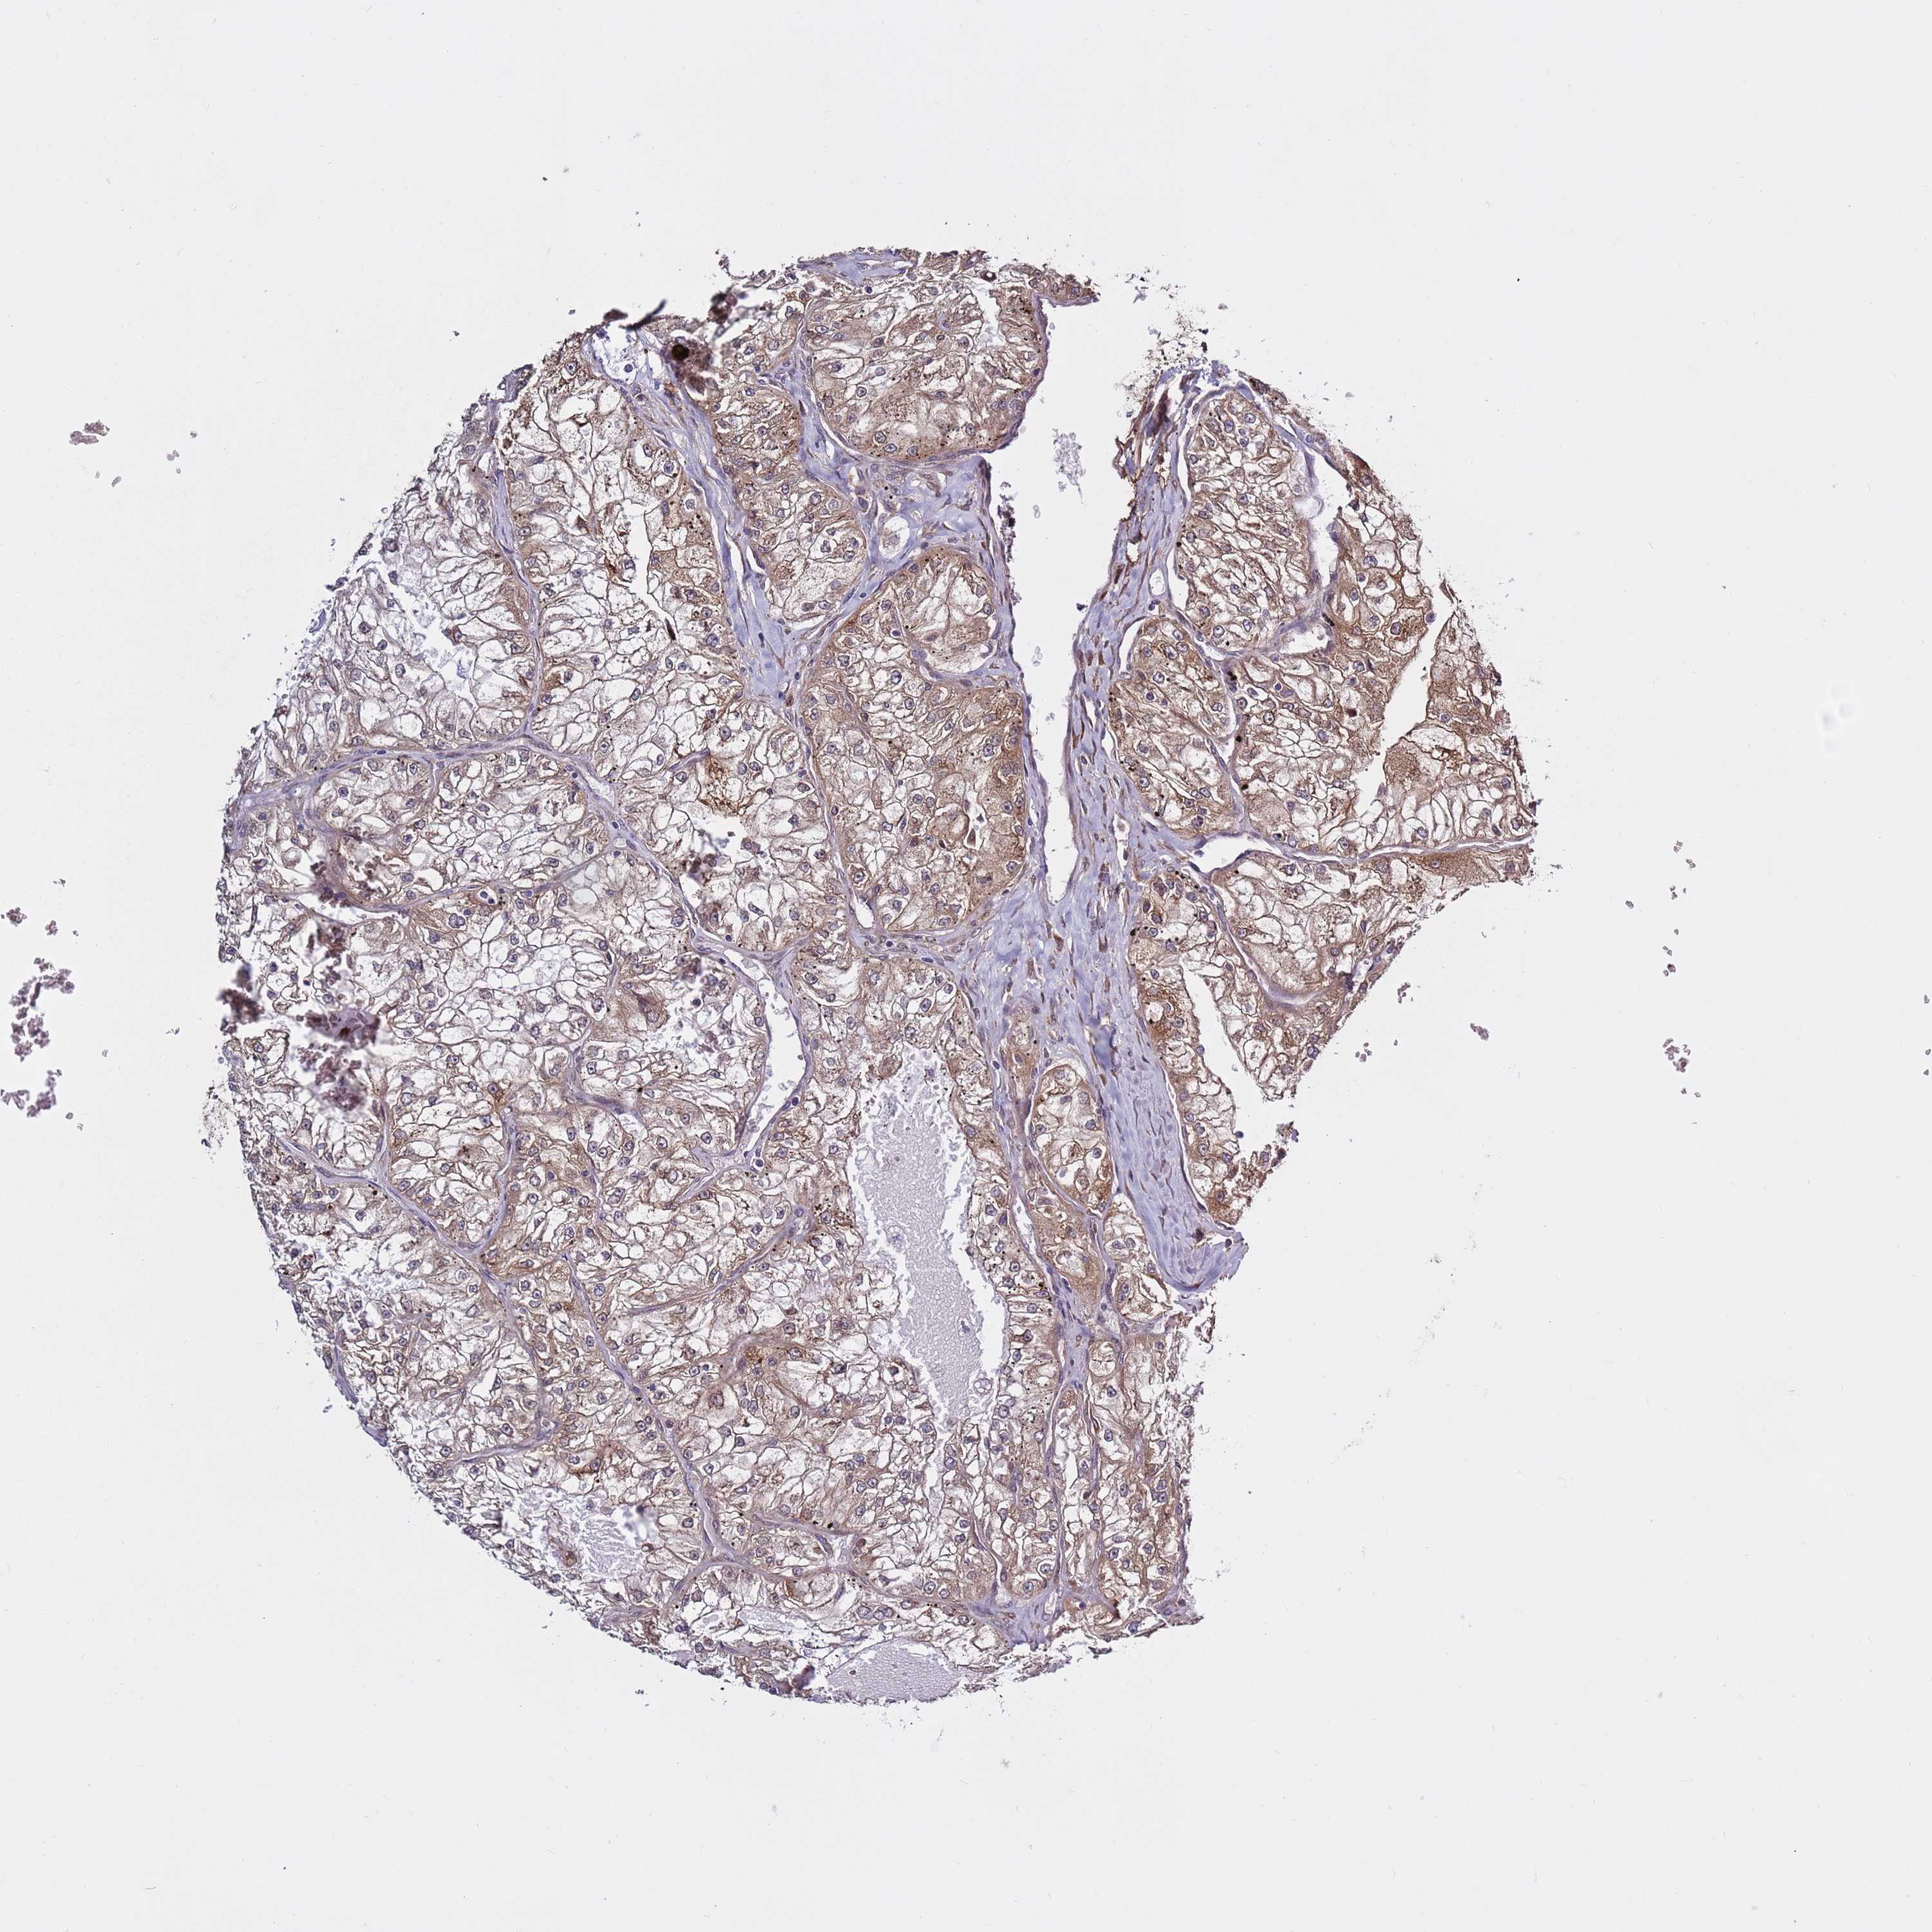

KIDNEY RENAL CLEAR CELL CARCINOMA (TCGA) - Interactive survival scatter ploti

The Survival Scatter plot shows the clinical status (i.e. dead or alive) for all individuals in the patient cohort, based on the same data that underlies the corresponding Kaplan-Meier plots. Patients that are alive at last time for follow-up are shown in blue and patients who have died during the study are shown in red.

The x-axis shows the expression levels (FPKM) of the investigated gene in the tumor tissue at the time of diagnosis. The y-axis shows the follow-up time after diagnosis (years). Both axes are complimented with kernel density curves demonstrating the data density over the axes. The top density plot shows the expression levels (FPKM) distribution among dead (red) and alive patients (blue). The right density plot shows the data density of the survived years of dead patients with high and low expression levels respectively, stratified using the cutoff indicated by the vertical dashed line through the Survival Scatter plot. This cutoff is automatically defined based on the FPKM cutoff that minimizes the p-score. The cutoff can be changed by dragging the vertical line or by entering a cutoff value in the square labeled "Current cut-off".

Under the Survival Scatter plot the p-score landscape (black curve; left axis) is shown together with dead median separation (red curve; right axis). Dead median separation is the difference in median mRNA expression between patients who have died with high and low expression, respectively. It is calculated as follows: median FPKM expression of dead patients with high expression - median FPKM expression of dead patients with low expression. This is intended to aid the user in visually exploring custom cutoffs and the associated p-scores and dead median separation.

Individual patient data is displayed and can be filtered by clicking on one or more of the category buttons on the top of the page. Categories describing expression level and patient information include: high, low, alive, dead, female, male and tumor stages. The scale of the x-axis can be toggled between linear and log-scale by clicking on the "x log" button. Mouse-over function shows TCGA ID, patient information and mRNA expression (FPKM) for each patient.

& Survival analysisi

Kaplan-Meier plots summarize results from analysis of correlation between mRNA expression level and patient survival. Patients were divided based on level of expression into one of the two groups "low" (under cut off) or "high" (over cut off). X-axis shows time for survival (years) and y-axis shows the probability of survival, where 1.0 corresponds to 100 percent.

PRKAB2 is not prognostic in Kidney Renal Clear Cell Carcinoma (TCGA)

Best expression cut offi

Based on the FPKM value of each gene, patients were classified into two groups and association between prognosis (survival) and gene expression (FPKM) was examined. The best expression cut-off refers the FPKM value that yields maximal difference with regard to survival between the two groups at the lowest log-rank P-value. Best expression cut-off was selected based on survival analysis .

When clicking on this number, the vertical dashed line indicating cut-off, the interactive survival plot, and the Kaplan-Meier curve will be adjusted to show results based on the best expression cut-off.

: 4.24

TCGA RNA samplesi

RNA-seq data is reported as average FPKM (number Fragments Per Kilobase of exon per Million reads), generated by the The Cancer Genome Atlas (TCGA) .

Normal distribution across the dataset is visualized with box plots, shown as median and 25th and 75th percentiles. Points are displayed as outliers if they are above or below 1.5 times the interquartile range. FPKM values of the individual samples are presented next to the box plot.

Average pTPM 6.8

Number of samples 521